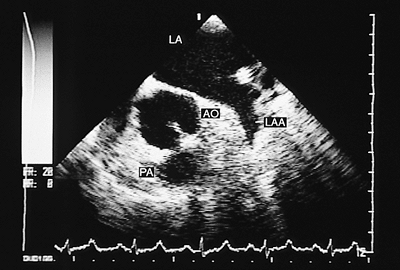

Congenitally Corrected Transposition

In congenitally corrected transposition, both the A–V and the V–A connections are discordant. Associated defects, especially ventricular septal defect, either isolated or with pulmonary valve stenosis, are common, occurring in 70% to 90% of cases. Cardiac malpositions also are commonly associated and can make it difficult to obtain satisfactory transthoracic recordings. The study of these patients should include transesophageal and transgastric recordings, and the main findings are discussed in the following paragraphs (4).

In V–A discordance, identification of the great arteries is based on the bifurcation of the pulmonary artery. The parallel positions of the two vessels can be observed with monoplanar recordings taken at the level of the semilunar valves. When situs is solitus, the aorta is anterior and to the left and the main pulmonary artery posterior and to the right (Fig. 8.2.48). In situs inversus the aorta is anterior but to the right of the main pulmonary artery.

Direct visualization of the connection of the ventricles to the great vessels is facilitated by the use of biplanar transducers. In images in the longitudinal plane it is possible to visualize the connection of the posterior vessel (pulmonary artery) with the left ventricle, to corroborate mitral-pulmonary continuity and to demonstrate the connection between the anterior outflow tract (right ventricular) and the aorta.

FIGURE 8.2.48. Ventriculoarterial discordance. Transverse plane image. The aorta (AO) is identified by the origin of the right coronary artery (CA). The pulmonary artery (PA) is located behind and to the right of the aorta, and its turbulent flow is secondary to the coexistence of subvalvular pulmonary stenosis. LA, left atrium; LAA, left atrial appendage; RA, right atrium.